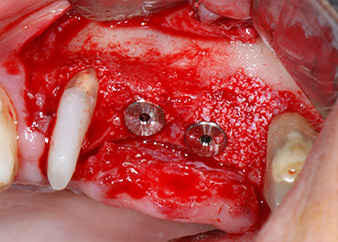

Implant beds were prepared at sites 25 and 26 with rotary instruments, used in a contra-angle handpiece with a 20 : 1 transmission ratio with an updated powerful implant motor (Implantmed, W&H) (Fig. 8).

The final preparation next to the sinus was again carried out with a piezoelectric instrument (Piezomed, insert S2).

Prior to implant placement, and following verification of an intact Schneiderian membrane (Fig. 9), the internal sinus floor was augmented at both implant sites by means of xenogeneic bone substitute material (Bio-Oss, Geistlich Biomaterials) (Fig. 10).

The implants (Restore, Keystone Dental, diameter 3,75 mm, length 8.0 mm) were placed with the implant motor

(Figs. 11 and 12).

Low speed insertion of implant 26

Fig. 11: Low speed insertion of implant 26 with a torque limitation of 35 Ncm.

ready for the cover screws

Fig. 12: Both implants in place and ready for the cover screws.